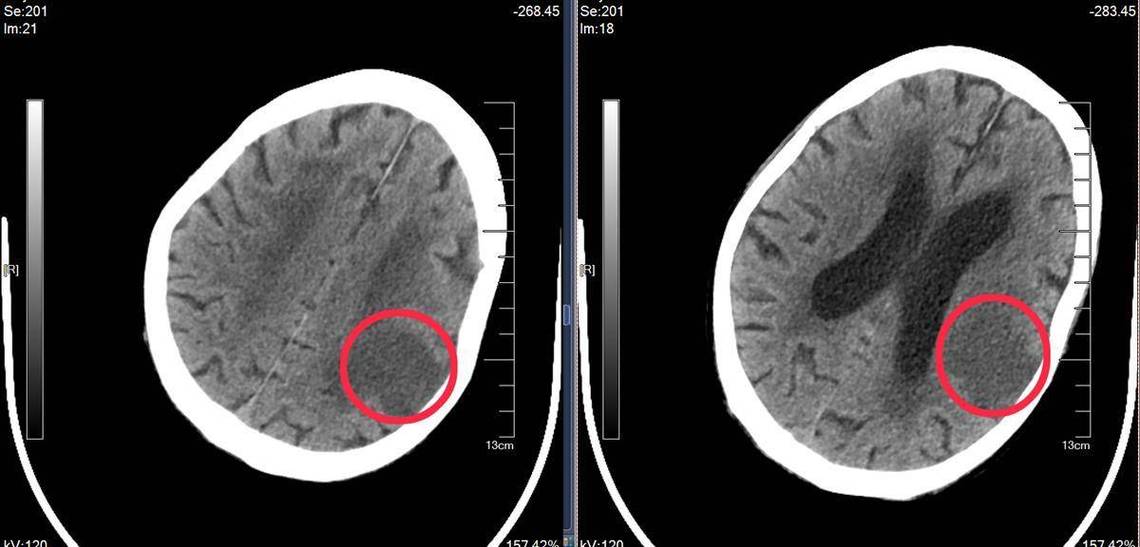

“新鲜”和“陈旧”可以共存: 很多老年患者,尤其是有高血压、糖尿病病史的,可能在一次新发脑梗的同时,脑内已经存在一个或多个陈旧性的梗塞灶,CT上会同时看到一个边界模糊的低密度灶(新鲜梗塞)和一个边界清晰的极低密度灶(陈旧梗塞)。